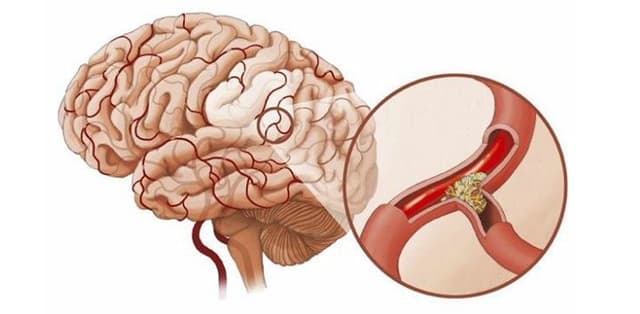

“Giải phẫu nhanh” bệnh lý đột quỵ tuyến yên

Đột quỵ tuyến yên là bệnh lý nguy hiểm, ảnh hưởng xấu tới tính mạng con người. Song, những thông tin liên quan tới căn bệnh cũng như nguyên nhân, triệu chứng vẫn còn khá ít ỏi. Hãy cùng chúng tôi tìm hiểu về bệnh lý này thông qua bài viết dưới đây. 1. Tổng […]